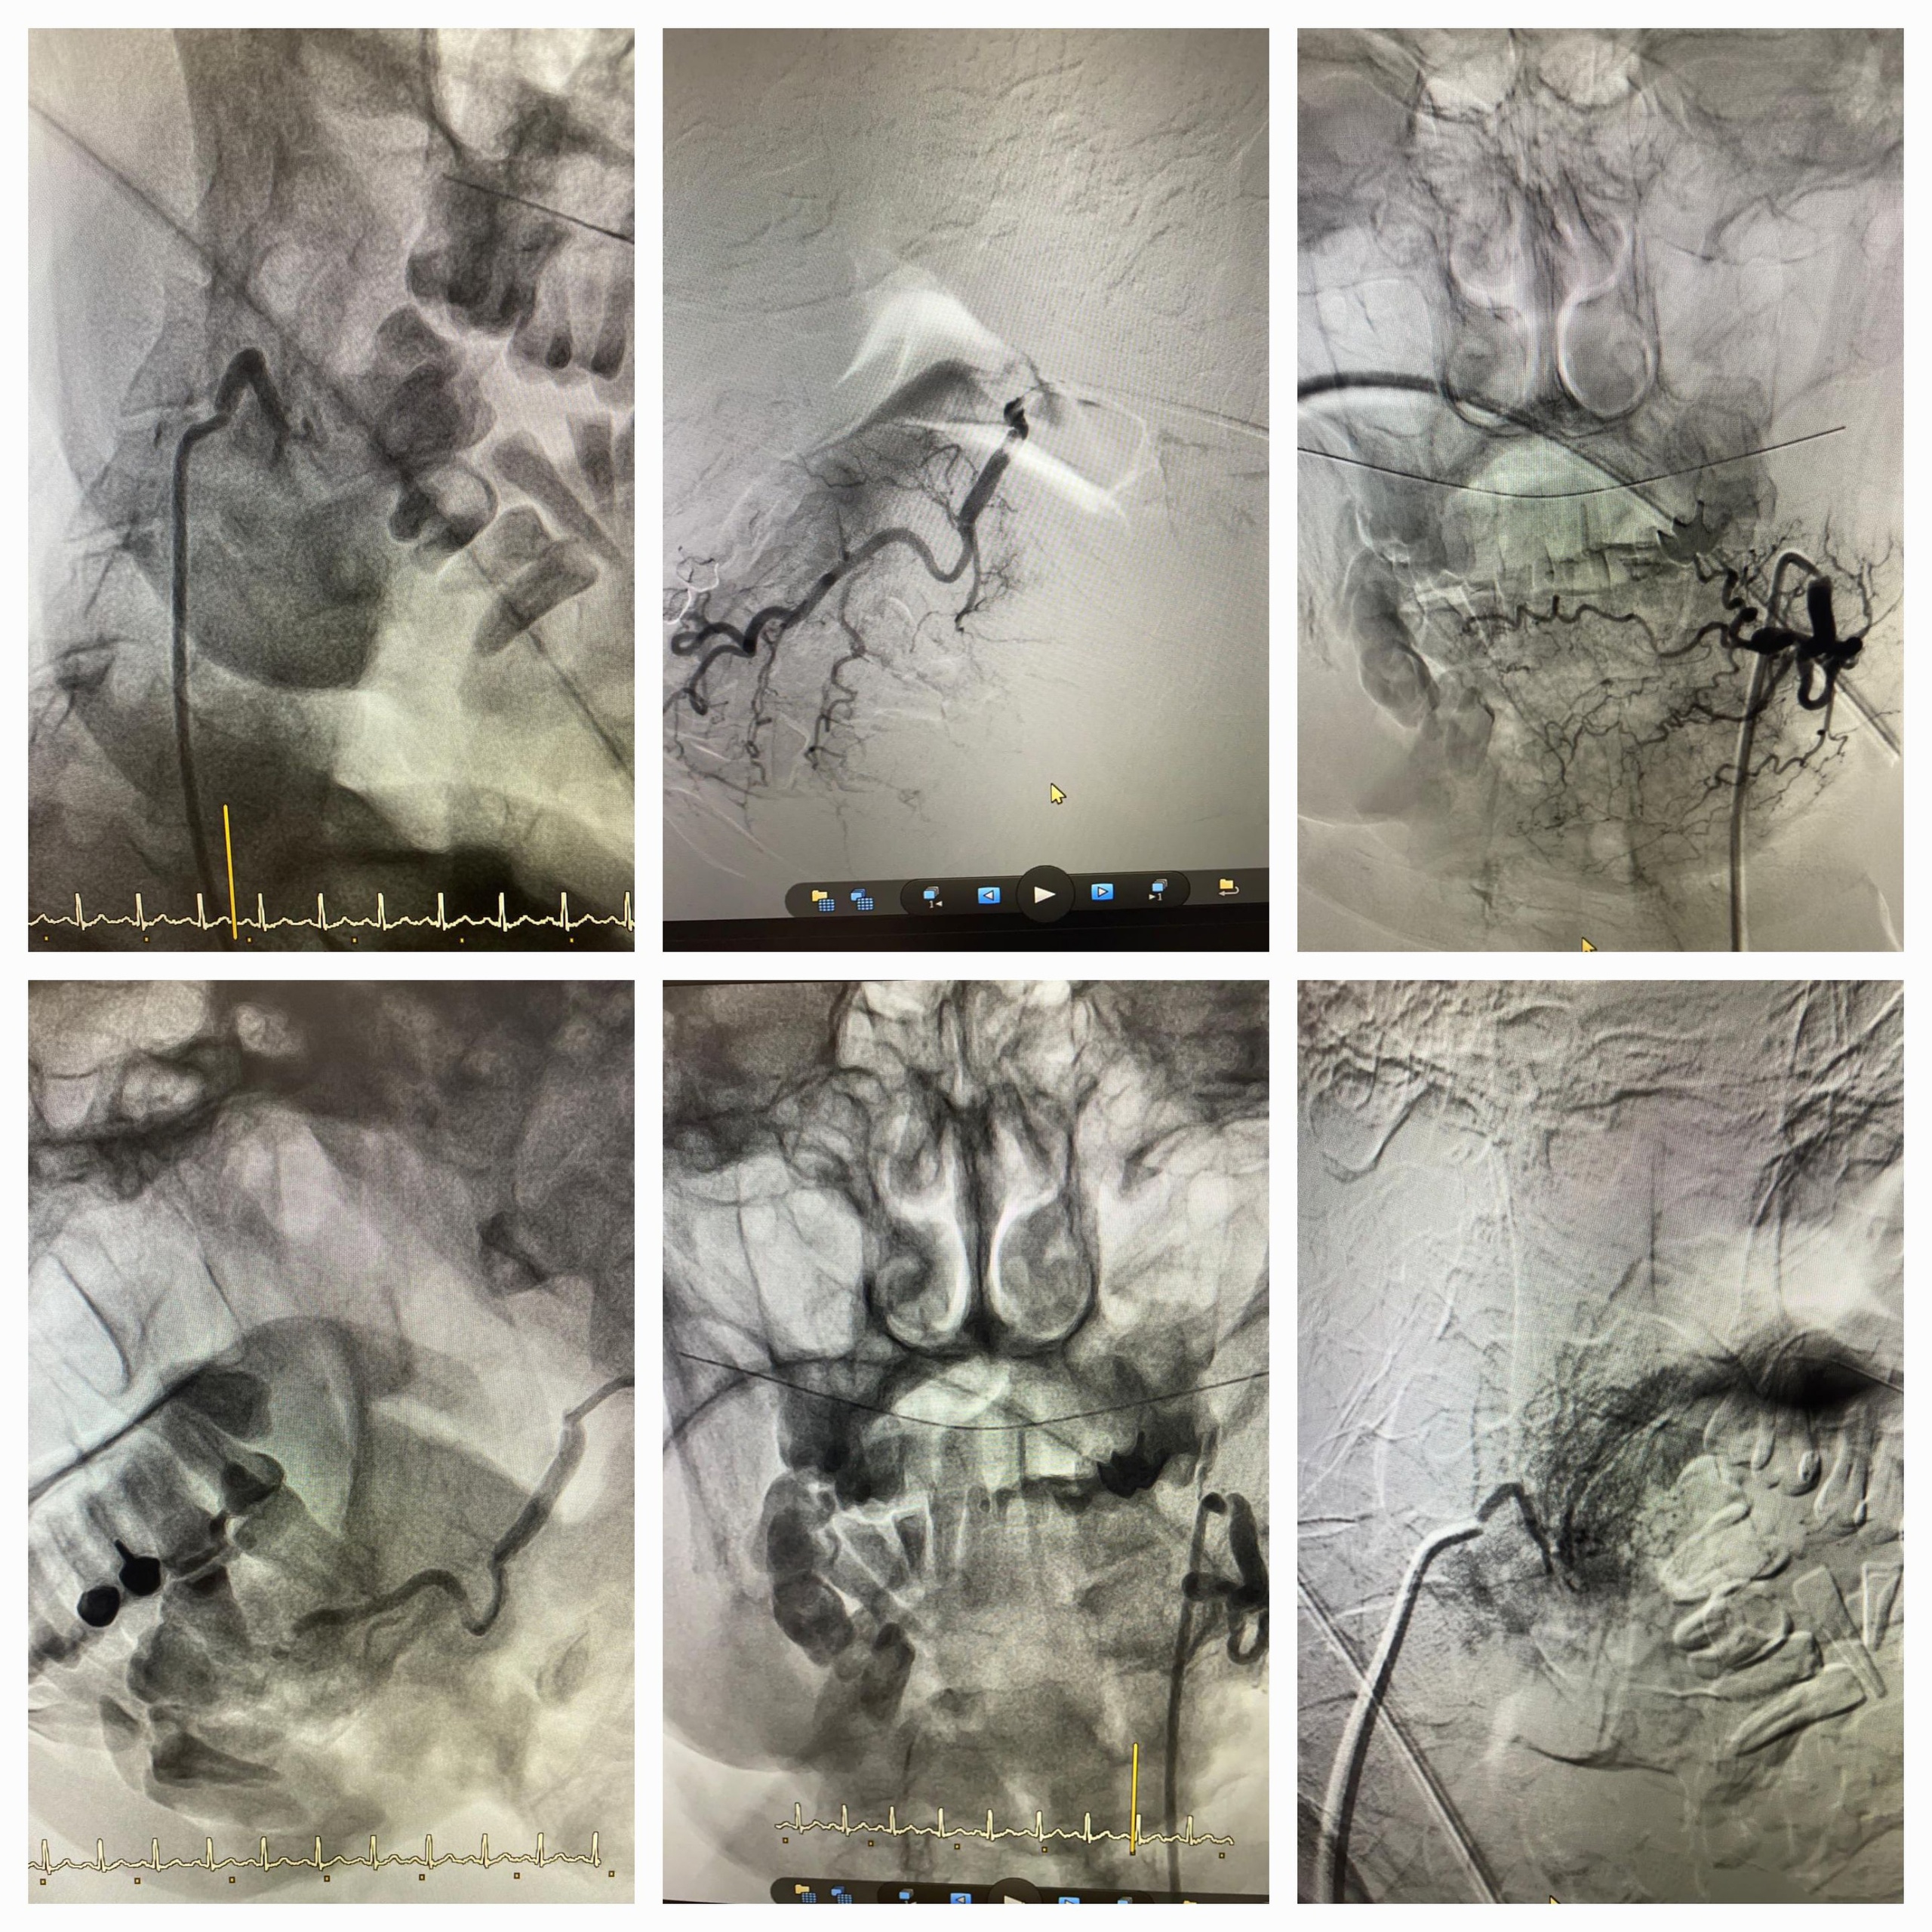

42-летний больной проходил лечение в областном онкологическом диспансере. Когда у него случилось рецидивирующее кровотечение опухоли шеи, его в срочном порядке доставили в клиническую больницу №6. На базе сосудистого центра врачи провели успешную эмблизацию ветвей наружной сонной артерии частицами поливинилалкоголя.